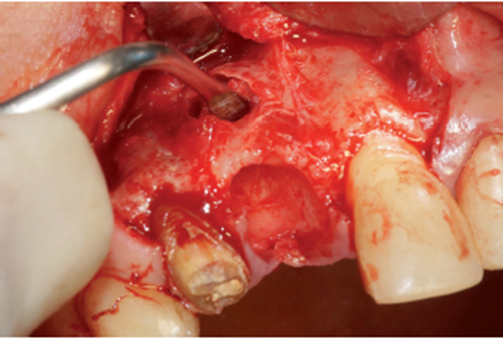

O procedimento cirúrgico foi iniciado através de uma anestesia infiltrativa com articaína 4%. Foram realizadas incisões relaxantes (Figura 4) para expor o leito cirúrgico e, consequentemente, a lesão periapical (Figura 5). Após o deslocamento do retalho, foi realizada a exodontia de forma atraumática (Figura 6) e na sequência, foi feita a curetagem do alvéolo removendo todo o tecido de granulação (Figura 7). Uma vez realizada a toalete do leito cirúrgico (Figuras 8 e 9), o implante Cone Morse Due Cone de 3.5 X 13 mm (Implacil De Bortoli) foi instalado seguindo o melhor posicionamento dentro do rebordo residual, conforme planejado (Figuras 10 e 11). Em sequência, foi realizada a instalação do Cover Screw (Figura 12) e o preenchimento do defeito ósseo com biomaterial (Bio-Oss 0,25), conforme figuras 13 e 14). O fechamento foi realizado com membrana de PTFE-d (Cytoplast TXT–200, Osteogenics – Lubbock TX, EUA), customizada para ser adaptada sobre o defeito ósseo, estendendo-se de 3 a 5 mm da margem do defeito ósseo e intencionalmente exposta (Figura 15). A sutura foi realizada com fio de PTFE (Cytoplast), como podemos observar na figura 16, e instalado um provisório adesivo na região (Figura 17).